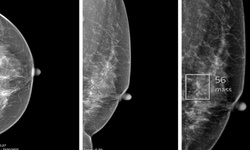

Phát hiện sớm ung thư vú nhờ công nghệ AI

Ung thư - 08/10/2025 12:02SKĐS - Ung thư vú đang ngày càng trẻ hóa. Nếu trước đây bệnh chủ yếu gặp ở phụ nữ trên 45 tuổi, thì nay nhiều ca được phát hiện ở độ tuổi 30–40, thậm chí dưới 30 tuổi. Tuy nhiên, ung thư vú có thể phát hiện sớm và điều trị hiệu quả.

PGS.TS Lương Ngọc Khuê: Đưa AI chẩn đoán hình ảnh giúp phát hiện ung thư giai đoạn sớm

Y tế - 13/01/2024 18:44SKĐS - PGS.TS Lương Ngọc Khuê cho hay, việc đưa AI trong hệ thống chẩn đoán hình ảnh giúp các bác sĩ tầm soát phát hiện các bệnh ung thư phổ biến ở giai đoạn sớm ở Việt Nam.